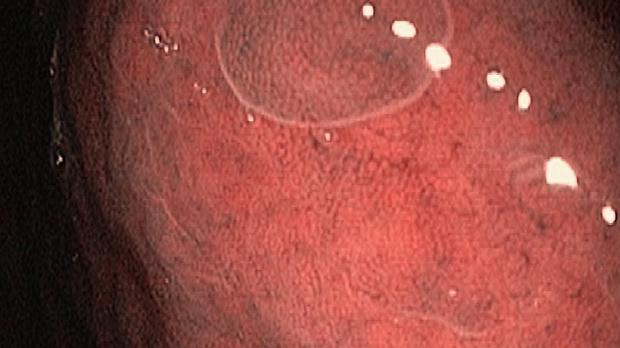

Появление ультратонких гастроскопов с высоким разрешением и технологией NBI (оптического узкоспектрального режима) компания OLYMPUS сделала возможной гастроскопию экспертного уровня под местной анестезией, без наркозных рисков.

Ультратонкие гастроскопы GIF-XP170N и GIF-XP190N с параметром оптики Close Focus, который позволяет приближаться к слизистой на минимальную глубину резкости до 2 мм, обеспечивают качество изображения, сопоставимое с аппаратами экспертного класса.

Использование в ежедневной рутинной практике современных ультратонких эндоскопов высокого разрешения с технологией оптического узкоспектрального режима (NBI® OLYMPUS™) под местной анестезией позволило полностью обеспечить соответствие критериям качества выполнения эндоскопических исследований, определенным ESGE. Данный метод комфортен для пациента под местной анестезией, безопасен, является простой и удобной альтернативой ЭГДС под седацией, что особенно важно в амбулаторных условиях.